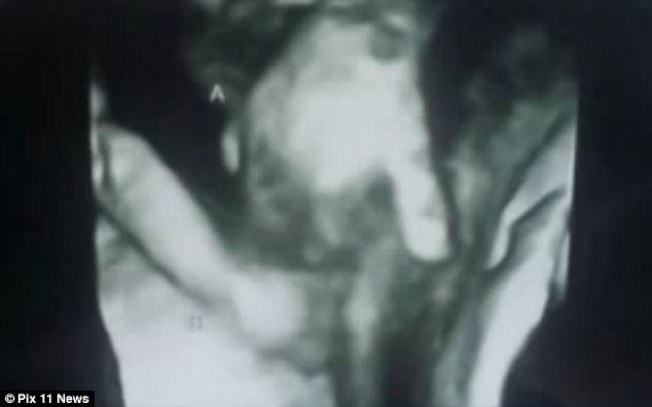

图为超声波显示,一个垂死胎儿握住另一双胞胎的手。(每日邮报)

在第六周接受超声波检查时,麦金泰夫妇得知他们取名梅森的男胎儿,心脏有个洞,大脑也不正常。他只重9盎司,双胞胎姊妹玛蒂琳则重2磅,而且持续健康成长。麦金泰夫妇学习接受这个事实时,医护人员注意到超声波出现一个情况:小小的梅森紧紧握住玛蒂琳的手。这个令人感动的图像,给将永远看不到他的父母带来安慰。